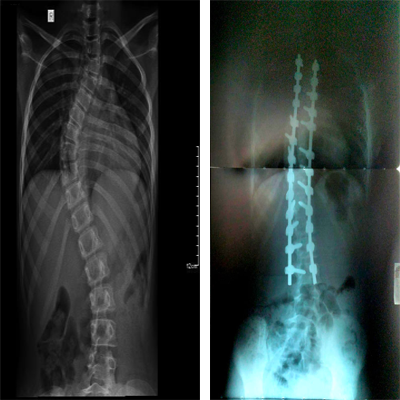

. Surgical treatments for scoliosis (scoliosis)

Scoliosis is a common problem in children and adolescents. Fortunately, surgical intervention is rarely necessary. One of the means of effective control of this disease is strengthening and physiotherapy. We offer thoracic, lumbar and sacral (TLSO) splint and immobilizer, rego chino belt and exercise physiotherapy specifically for the treatment of scoliosis. In severe cases, we resort to surgical options that correct the scoliosis while preserving the mobility of the spine.